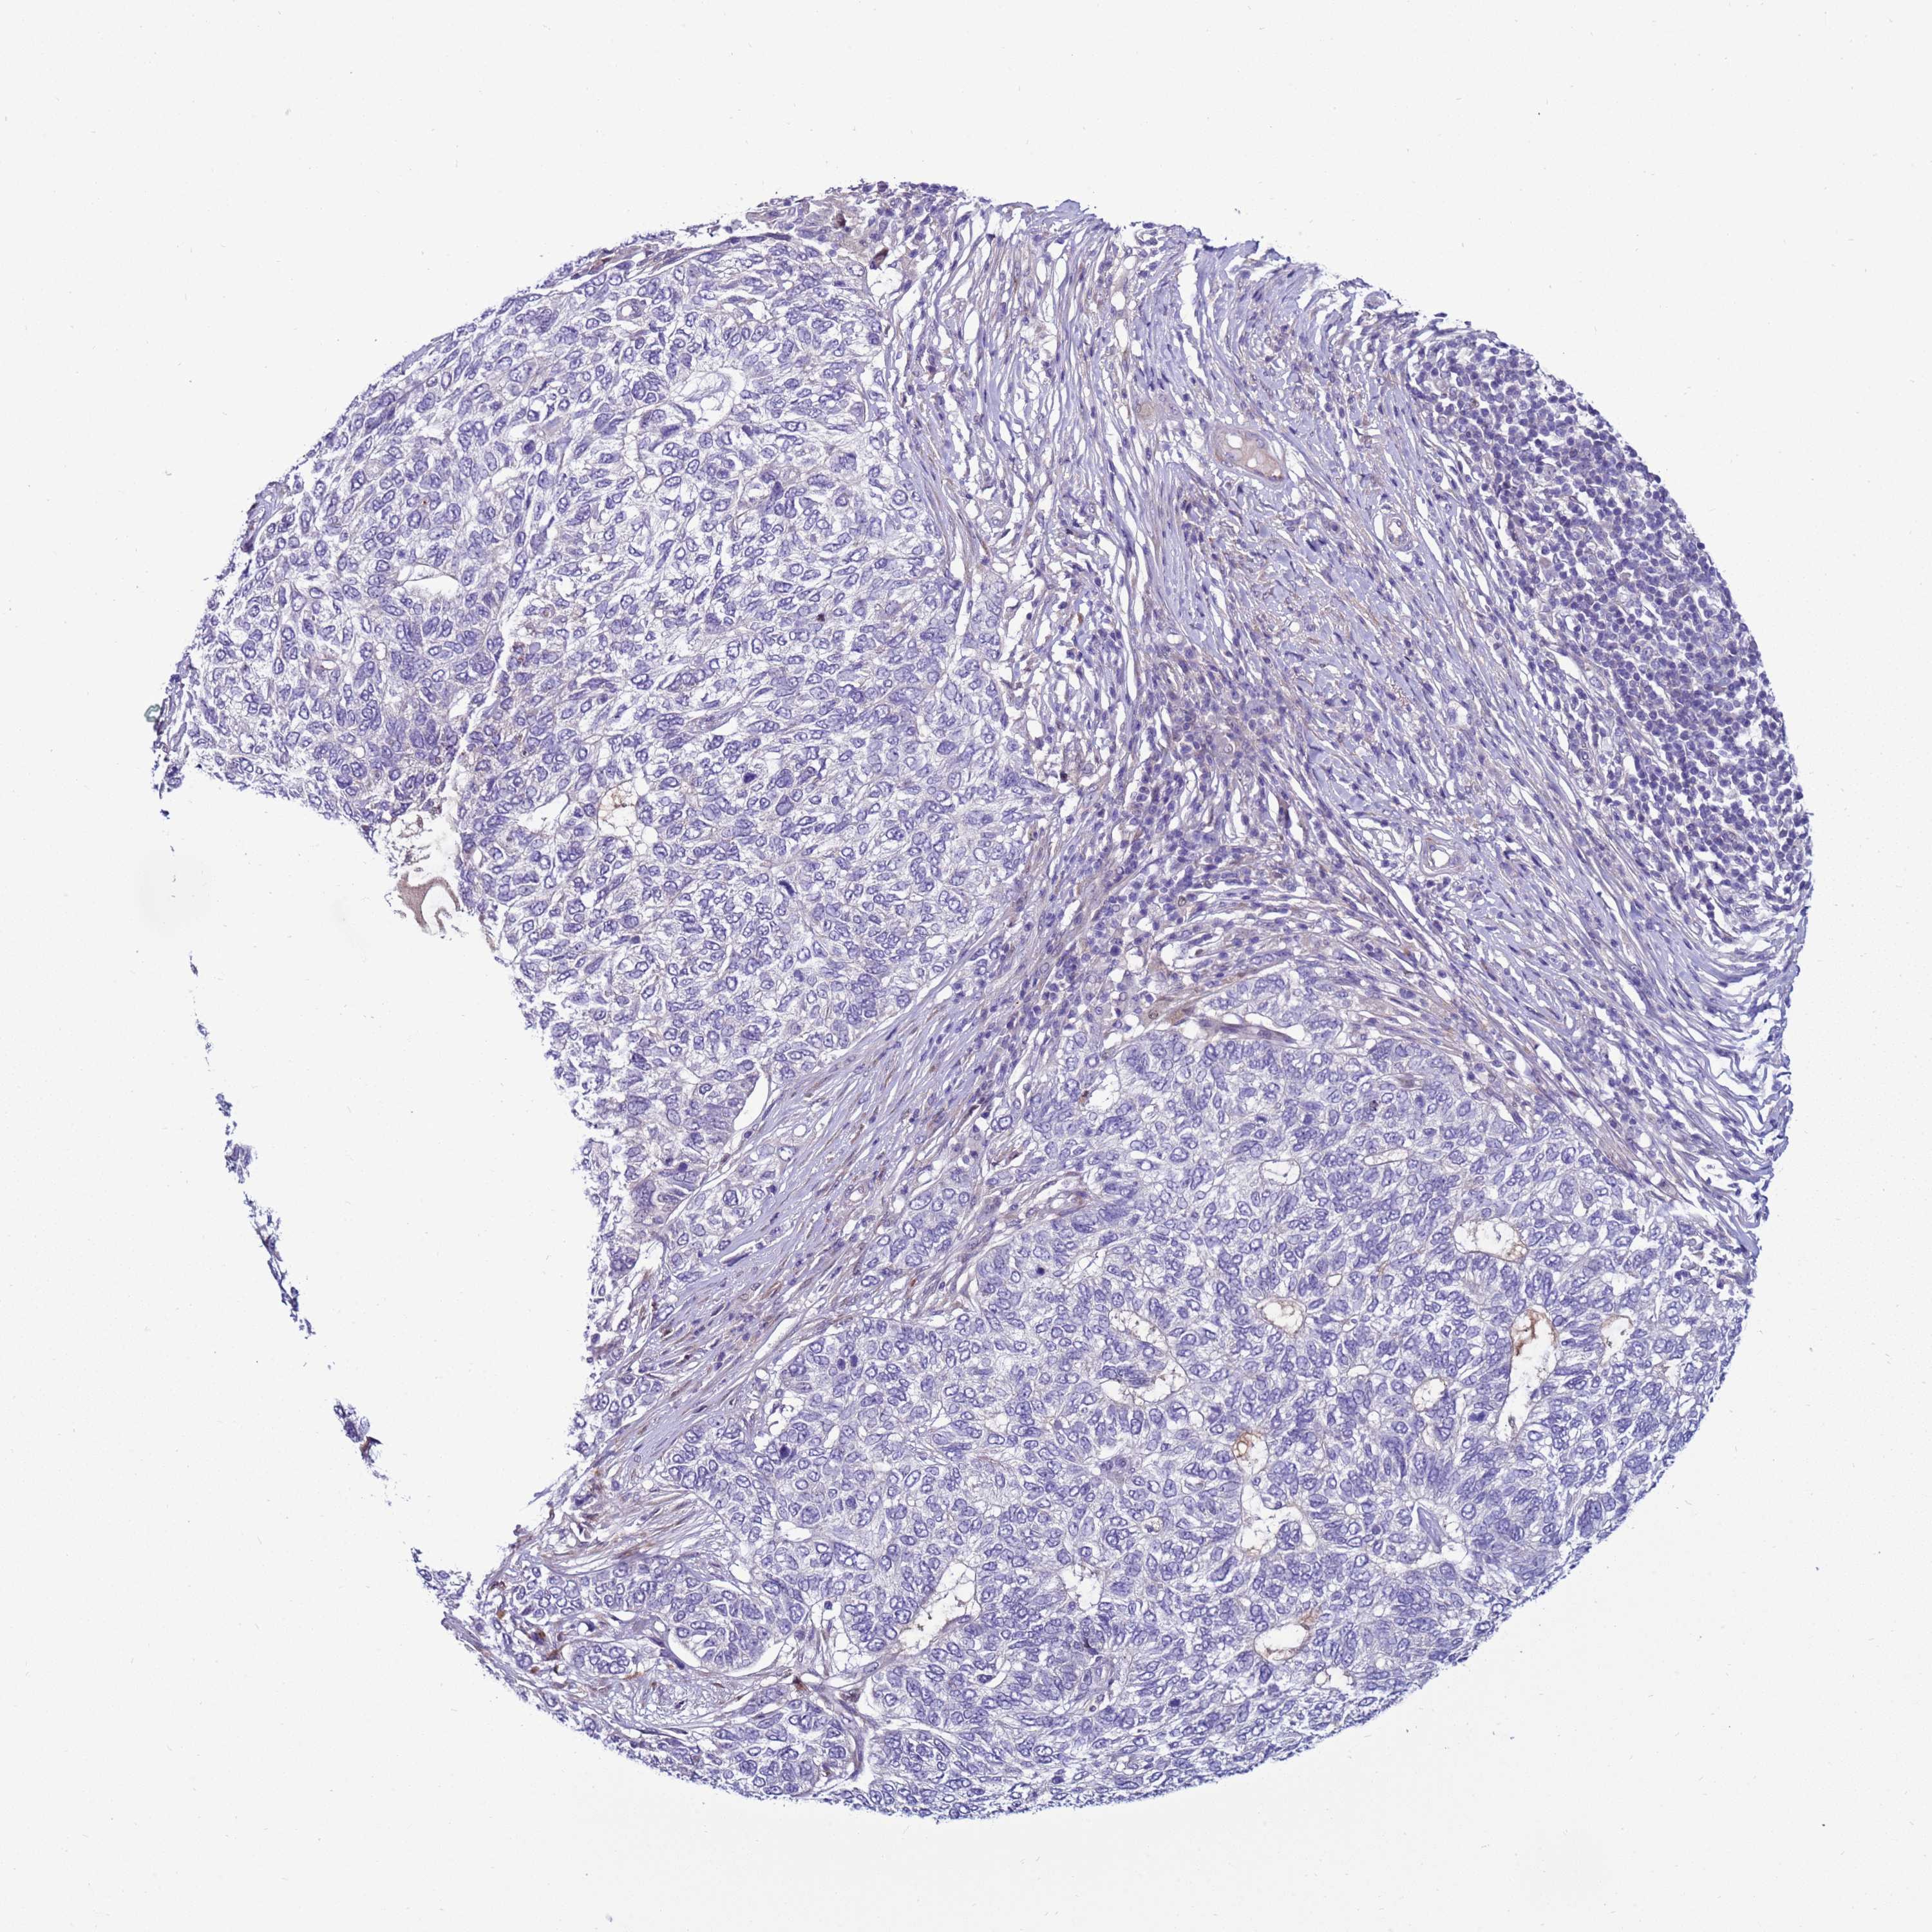

CANCER SKIN CANCER Show tissue menu

Basal cell and squamous cell cancer

SKIN CANCER - Protein expressioni

A mouse-over function shows sample information and annotation data. Click on an image to view it in a full screen mode. Samples can be filtered based on level of antibody staining by selecting one or several of the following categories: high, medium, low and not detected. The assay and annotation is described here.

Each image is clickable and will lead to virtual microscopy that enables deeper exploration of all samples and also displays staining intensity scores, fraction scores and subcellular localization as well as patient and tissue information for each sample.

Antibody HPA043704

Staining

High

Medium

Low

Not detected

Intensity

Strong

Moderate

Weak

Negative

Quantity

>75%

75%-25%

<25%

None

Location

Nuclear

Cytoplasmic/membranous

Cytoplasmic/membranous,nuclear

Basal cell carcinoma

Squamous cell carcinoma, NOS

Squamous cell carcinoma, metastatic, NOS